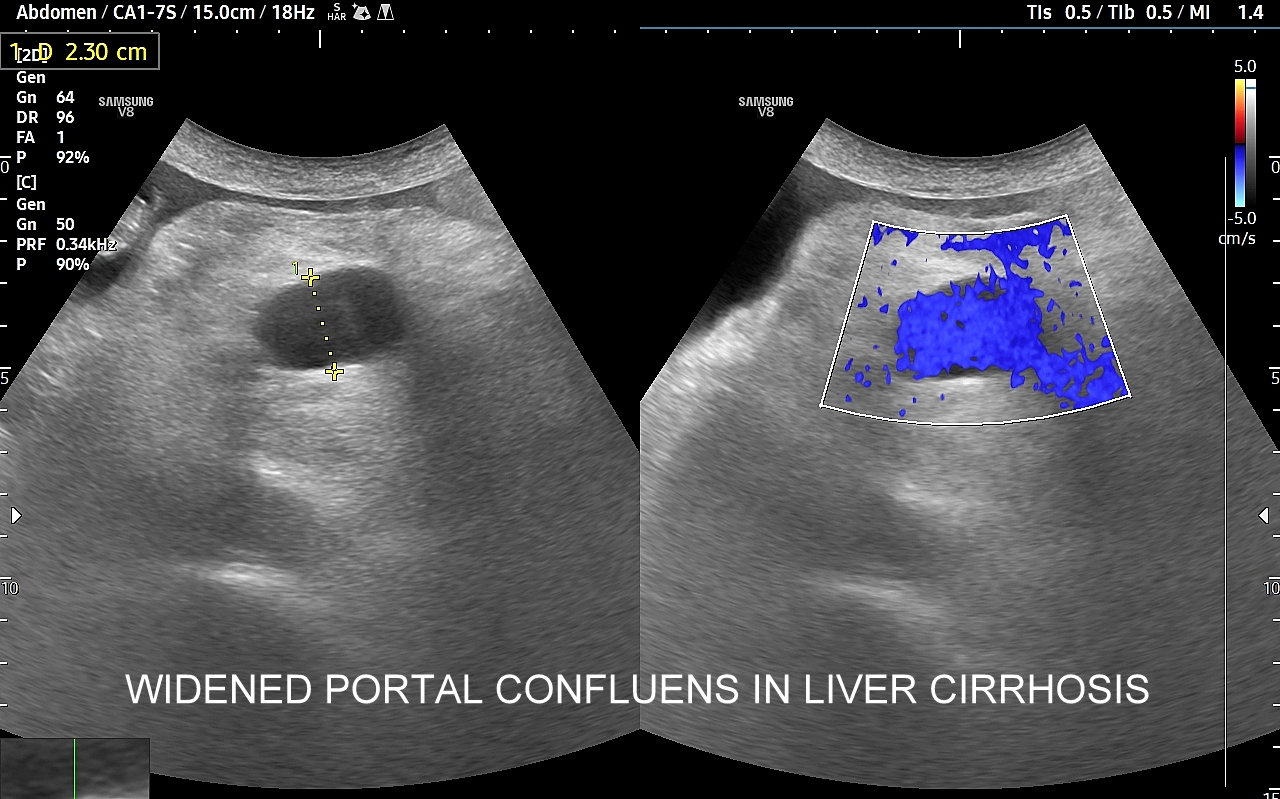

Wątroba posiada unaczynienie różnego typu, a każde o swojej indywidualnej charakterystyce. Są to unaczynienie tętnicze, unaczynienie wrotne (żyła wrotna i jej dopływy z narządów jamy brzusznej), odpływ żylny poprzez żyły wątrobowe. W USG Doppler przepływów wątrobowych bada się każdy z tych układów.

Badanie USG Doppler układu wrotnego wątroby łącznie ze standardową oceną morfologii wątroby i śledziony wykonywane jest najczęściej w ramach diagnostyki nadciśnienia wrotnego, czyli podwyższonego ciśnienia krwi w żyle wrotnej, które może być przyczyną zagrażających życiu żylaków przełyku. Badanie dopplerowskie wątroby uzupełnia również diagnostykę marskości wątroby oraz służy wykrywaniu takich patologii jak zakrzepica w żyle wrotnej i jej dopływach, zakrzepica w żyłach wątrobowych, czy rozprzestrzeniające się nowotwory w naczyniach wątroby.